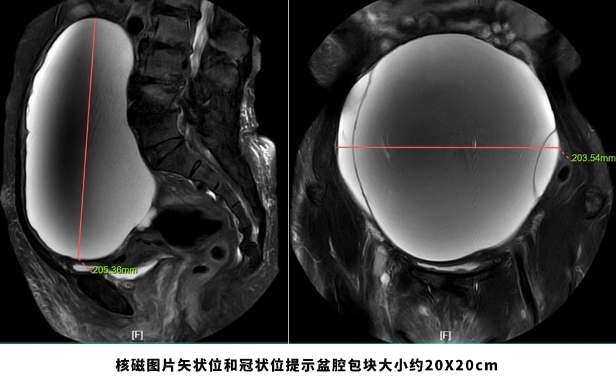

人民日报客户端:69岁老妇挺着“大肚子”来医院,检查后竟“怀”了个巨大肿瘤!